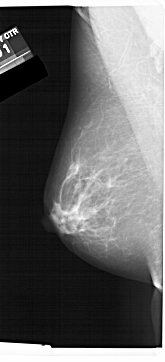

A_1456_1.LEFT_MLO

LEFT_MLO LINES 6871 PIXELS_PER_LINE 3121 BITS_PER_PIXEL 12 RESOLUTION 43.5 NON_OVERLAY